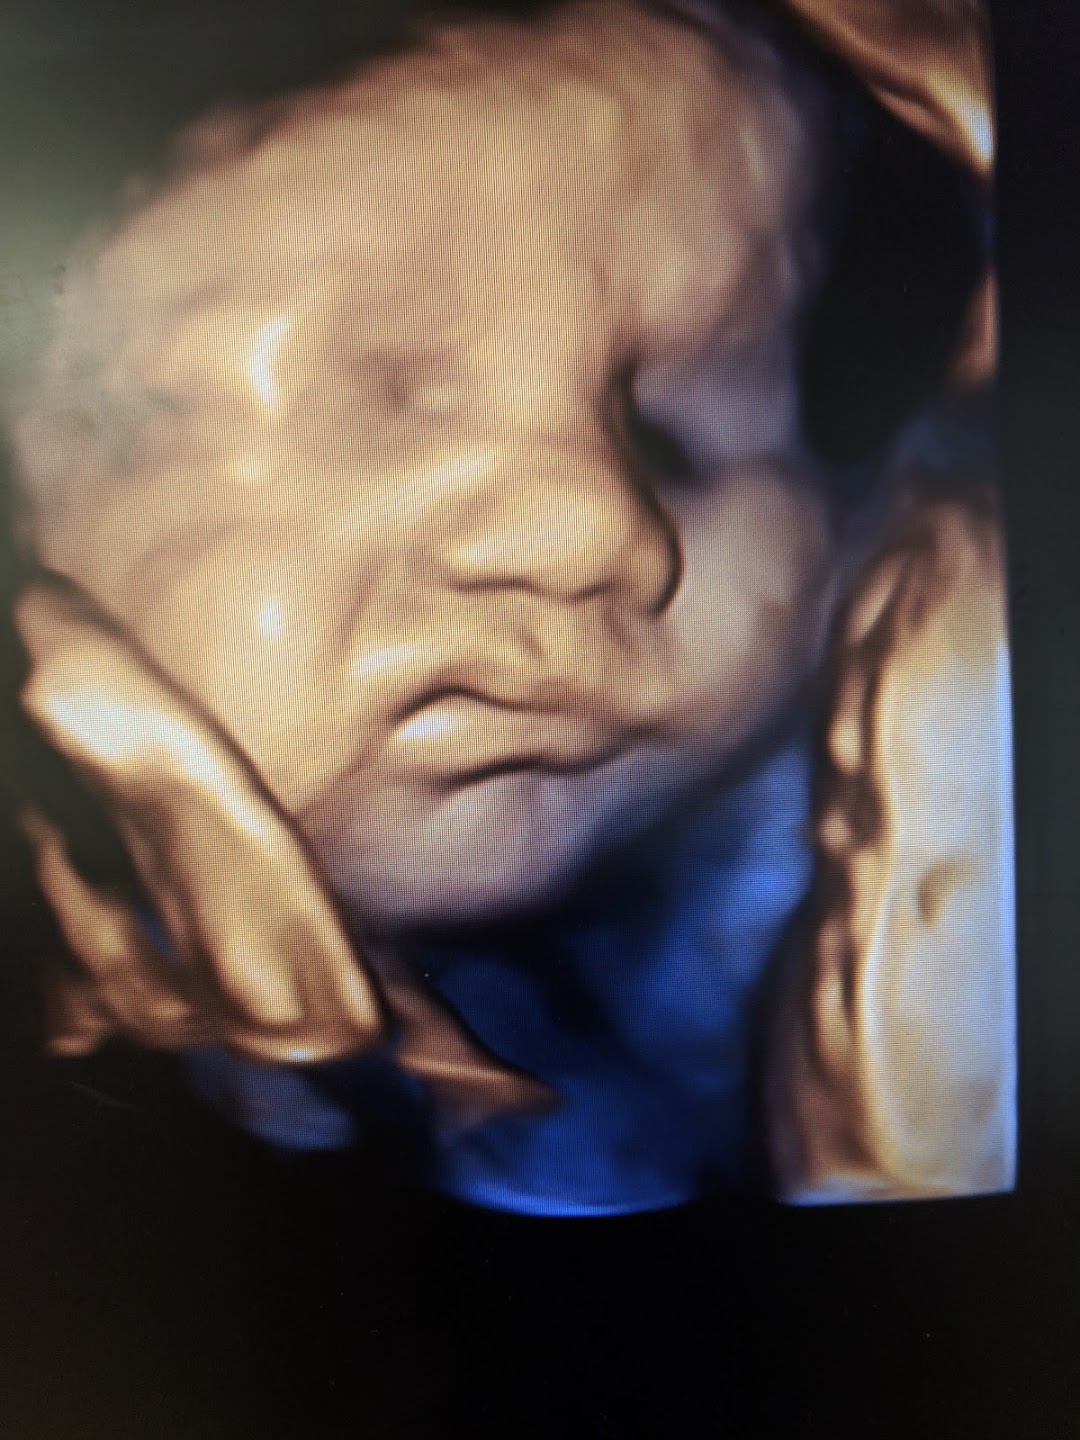

Sweet baby face louisville ky. March 1 2020. Sweet Baby Face is a 3D 4D Ultrasound and Baby Boutique in Louisville Elizabethtown KY. See your child in more depth and detail.

Pregnancy and Childbirth Service Near Sweet Baby Face. They give you a much clearer view of your child than the traditional 2D ultrasound you may even see if your baby has you or your partners features. Company Profile Contact information Current and former Employee directory Corporate history statetax IDs.

We do 2D 3D 4D HD5D elective ultrasound images in Louisville Elizabethtown. Millions of Products Top Brands. Combining cutting-edge technology with a spa theater environment we bring unbelievable images of your unborn baby to life.

See reviews photos directions phone numbers and more for Sweet Baby Face locations in Glenview KY. Opened in 2010 in Louisville Ky and a location in Elizabethtown in 2015. Come see them at Sweet Baby Face so you can see your Sweet Babys Face.